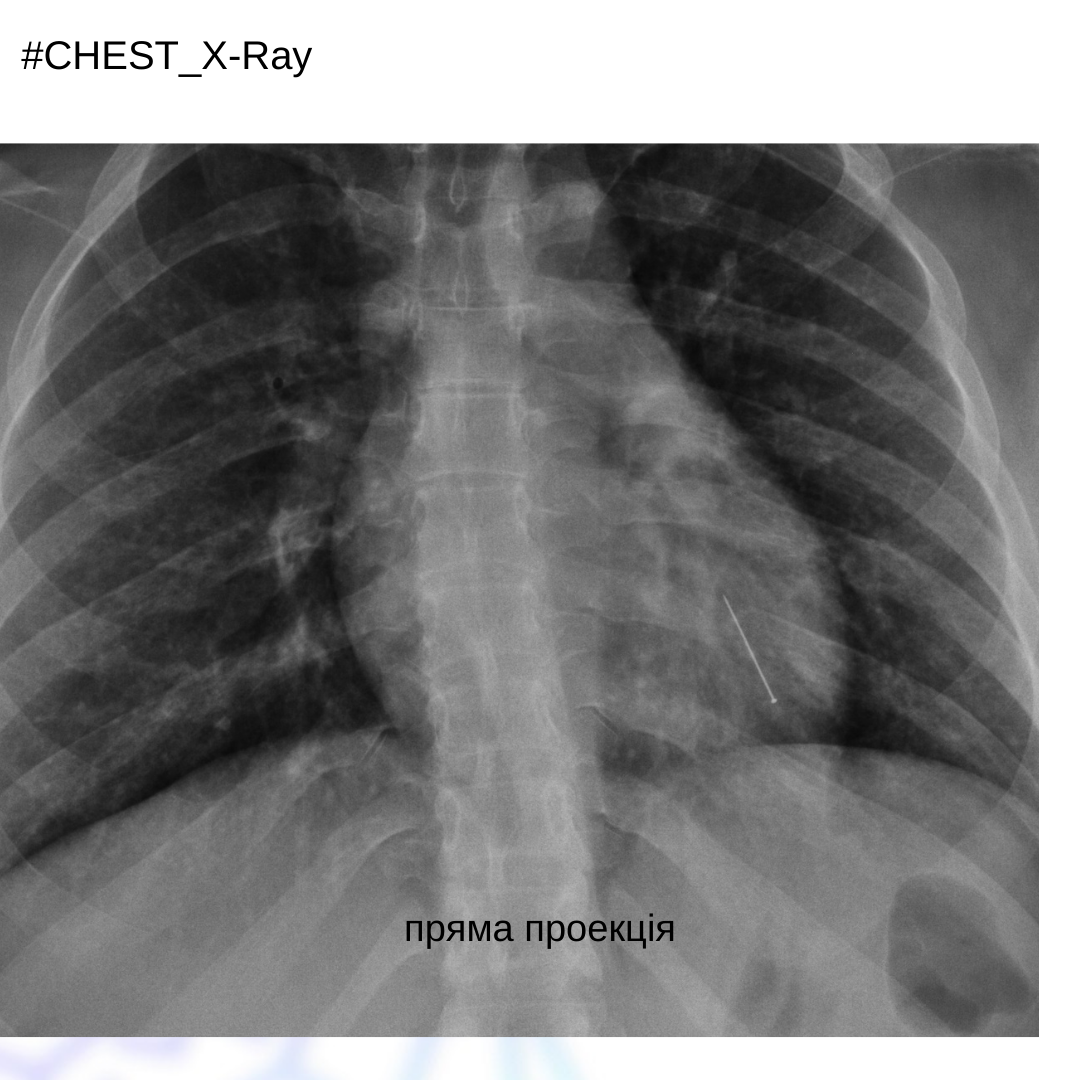

Жінка 30 років, зі скаргами на кашель, задишку, появу хрипів, які виникли після вдихання голки під час шиття.

На рентгенограмі ОГК в прямій та боковій проекціях візуалізується стороннє тіло у передньобазальному сегменті лівої нижньої долі. Пневмоторакс не візуалізується.

Висновок: аспірація сторонніх тіл до дихальних шляхів діагностується на ранніх стадіях, оскільки це викликає такі симптоми, як задишка, хрипи, кашель як у цього пацієнта. У деяких випадках діагностика може бути складною через відсутність типових симптомів або якщо чужорідне тіло не рентгеноконтрастне.